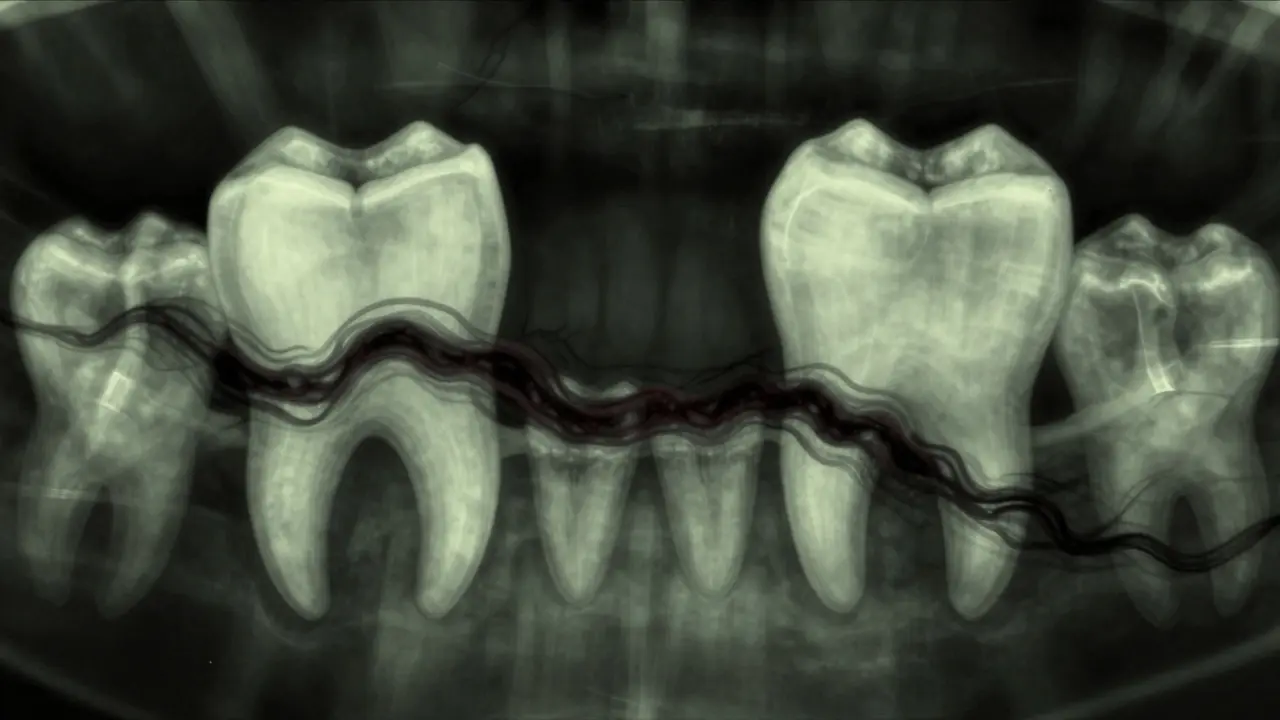

Skrytý mezizubní kaz mezi zubem moudrosti a sousedním zubem, znázorněný temnými stíny šířícími se po sklovině.

3D rentgenový snímek impaktovaného zubu moudrosti tlačícího na sousední zub, s označenými oblastmi poškození.